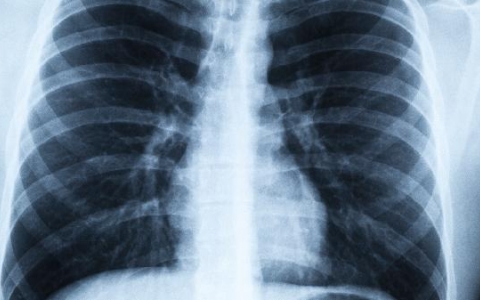

肺结节ct怎样描述才严重

肺结节在CT扫描中的描述能帮助我们判断其严重程度。通常情况下,肺结节的大小、形态、边缘状况以及是否存在分叶等特征是评估的重要指标。如果肺结节较大,并且伴有恶性特

肺结节ct影像鉴别诊断

肺结节的CT影像鉴别诊断是一个复杂而重要的过程,主要包括对良性结节和恶性结节的区分。良性结节可能是感染性结节、错构瘤或真菌感染,而恶性结节则可能是原发性肺癌或转

肺结节ct能分辨出来吗

肺结节在CT检查中通常是可以分辨出来的,但具体的判断还需要考虑结节的大小、形态和边缘的情况等因素。如果发现肺结节,建议尽快就医,通过进一步的检查和医生的建议来确

肺结节ct胶片上能看准吗

肺结节在CT胶片上通常能被识别,但要完全确诊其性质,病理学检查是必不可少的。CT扫描提供了关于肺部结节的大小和形态的重要信息,但它并不能明确区分结节是良性还是恶

肺结节ct怎么看懂结果

肺结节的CT检查结果可以通过观察结节的大小、形态、边缘以及是否有分叶等特征来初步判断其性质。一般来说,如果结节较小,直径小于5毫米,通常是良性病变的可能性较大,

肺结节ct影像片怎么看

看懂肺结节的CT影像片,主要是从大小、形态、边缘和内部密度几个方面入手。这些特征能帮助我们初步判断结节的性质。如果你有任何不适症状,最好尽快就医以获得专业的诊断